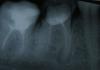

Doc Опубликовано 1 марта, 2011 Поделиться Опубликовано 1 марта, 2011 А этот снимок ПОСЛЕ лечения каналов??? По виду как будто бы ДО. Если это максимум того, что Вам могут сделать с каналами, то лучше уж имплантат. Ссылка на комментарий

Snesha Опубликовано 1 марта, 2011 Автор Поделиться Опубликовано 1 марта, 2011 (изменено) А этот снимок ПОСЛЕ лечения каналов??? По виду как будто бы ДО. Если это максимум того, что Вам могут сделать с каналами, то лучше уж имплантат.Да, снимок после, до этого у другого врача было еще хуже. Доктор сказал, что он конечно может еще пройти 2 более коротких канала, но он не видит в этом смысла, каналы очень узкие, нужно долго ковырять. Правда, дальнейшую работу по восстановлению зуба я не у него буду делать, только если металлическую коронку, он еще прдлагал 2 штифта в корни + нарастить световую пломбу и так походить, но я так понимаю, это совсем ненадежная конструкция. Думала пролечить у него каналы, так как это не так дрого, как в соседнем городе и проще доехать, вы считаете, что придется и эту работу переделывать?Если нужна имплантация, то можно пока поставить металлическую коронку временно, чтобы денег собрать или не стоит. Будет ли она вообще держаться без вкладки? Изменено 1 марта, 2011 пользователем Snesha Ссылка на комментарий

Doc Опубликовано 1 марта, 2011 Поделиться Опубликовано 1 марта, 2011 Да, снимок после, до этого у другого врача было еще хуже. Доктор сказал, что он конечно может еще пройти 2 более коротких канала, но он не видит в этом смысла, каналы очень узкие, нужно долго ковырять. Правда, дальнейшую работу по восстановлению зуба я не у него буду делать, только если металлическую коронку, он еще прдлагал 2 штифта в корни + нарастить световую пломбу и так походить, но я так понимаю, это совсем ненадежная конструкция. Думала пролечить у него каналы, так как это не так дрого, как в соседнем городе и проще доехать, вы считаете, что придется и эту работу переделывать?Если нужна имплантация, то можно пока поставить металлическую коронку временно, чтобы денег собрать или не стоит. Будет ли она вообще держаться без вкладки? На такие каналы нельзя ставить вообще ничего, ни вкладку, ни коронку, ни железную коронку. Этот зуб - как мина замедленного действия, может рвануть в любую минуту. Не тратьте на него деньги, если в округе нет хорошего специалиста по каналам. Ссылка на комментарий

magnus2004 Опубликовано 1 марта, 2011 Поделиться Опубликовано 1 марта, 2011 6-ка кандидат на удаление. + В семерке нужно перелечить каналы, укрепить вкладкой и покрыть коронкой. Ссылка на комментарий

magnus2004 Опубликовано 1 марта, 2011 Поделиться Опубликовано 1 марта, 2011 В шестом зубе перфорация, скорее всего перелечить не выйдет. Разве что за очень большие деньги. Как вариант, дешевая штампованая коронка с последующим удалением. Уколы делать не надо, лучше кредит на имплант взять. Ссылка на комментарий

Bier Опубликовано 1 марта, 2011 Поделиться Опубликовано 1 марта, 2011 перфорация - дырка в неположенном месте. Делает прогноз на зуб сомнительным.Мое мнение, что лучше его удалить. Может не завтра, но удалить. Ссылка на комментарий

Grit-David Опубликовано 6 марта, 2011 Поделиться Опубликовано 6 марта, 2011 Зуб надо перелечить а то перейдет в хронический передонтит.Потом можно поставить вкладку и коронку обычную металлокерамику.Керамическая там не подойдет ,на разницу потавьте имплант не тяните а то придетс нращщивать котную ткнь.Более дтально рассмотрите каналы желательно на 3д нимке похоже там перфорация.Ели не дай бог это так то все зуб удаляется. Ссылка на комментарий